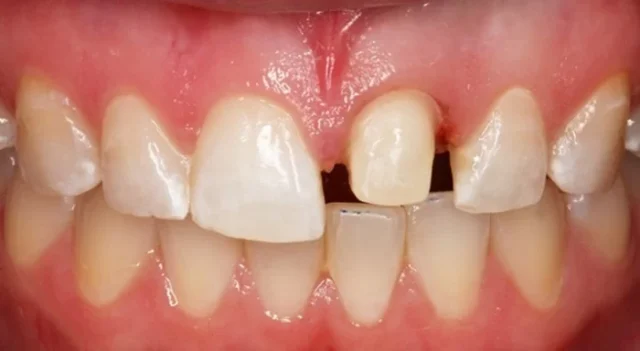

Phẫu thuật Cắt Răng

Trong một số trường hợp răng trông dài do nướu phát triển không đều hoặc thân răng quá lộ, bác sĩ có thể chỉ định phẫu thuật cắt nướu hoặc tạo hình mô nướu để cân đối lại tỷ lệ giữa răng và nướu. Thủ thuật này giúp cải thiện thẩm mỹ nụ cười, đồng thời hạn chế nguy cơ tích tụ vi khuẩn ở vùng chân răng. Việc thực hiện cần được thăm khám kỹ lưỡng để đảm bảo an toàn và đạt kết quả tối ưu.

Răng Dài Quá Mức

Khi nhận thấy răng lộ ra nhiều bất thường, nướu tụt rõ hoặc tỷ lệ răng – nướu mất cân đối, đó là dấu hiệu cần được kiểm tra chuyên môn. Tình trạng răng dài quá mức không chỉ ảnh hưởng đến thẩm mỹ mà còn làm tăng nguy cơ nhạy cảm răng và bệnh lý nha chu. Việc tham khảo ý kiến nha sĩ sẽ giúp xác định nguyên nhân chính xác và lựa chọn phương pháp điều trị phù hợp, tránh để tình trạng tiến triển nặng hơn.